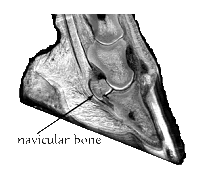

When the horse’s weight descends, the hoof is sandwiched between that load and the ground. It is meant to spread apart upon weight bearing, with the coffin bone dropping down like a trampoline. This is the natural shock-absorption feature of the hoof. The walls spread apart and the sole draws flat. Horses with this elasticity and hoof function are most adequately prepared to absorb shock and concussion. When metal is nailed in all around, how does the hoof perform its duty? Where is the shock absorbed? Most likely it is absorbed in the sensitive tissue of the hoof or further up the structure of the leg, which is what needs to be prevented. If we allow our horses to function more naturally they would not be showing increasing symptoms of pain and discomfort.

The metal shoe is nailed on when the hoof is in the air. It is at its smallest, most contracted shape. It is not weight-bearing or in movement, and is held firmly in this state by the metal – no expansion and nowhere for the coffin bone to descend. As the coffin bone pushes down under the horse’s weight, it is then bruising the solar corium which cannot expand and draw flat to get out of the way. This lack of flexibility and cushioning can cause problems with circulation, foot and joint pain and may cause damage to the structure of the foot in some cases. Not to mention put undue stress on the ligaments and tendons and irritate connective tissue. Metal horseshoes can also be very slippery and provide no traction. Think about this scenario when you are riding in a parade for instance. Your horse is pounding the pavement for a couple of hours. Maybe trotting some of that distance and his hooves, joints, ligaments, and tendons are feeling every step. Or, your horse gets overly excited or spooks and slips right out from under you.